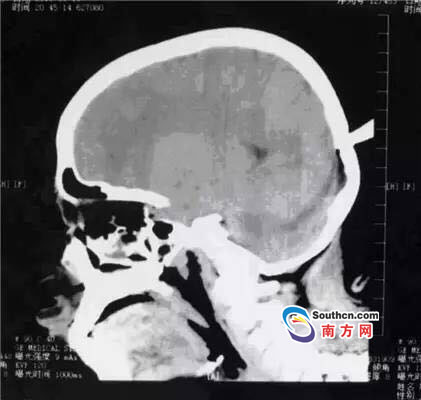

接到小玲受傷的消息,東莞市第三人民醫(yī)院急診科立即啟動了急癥危重患者搶救流程。急癥頭部CT顯示,飛鏢已穿透小玲的顱骨,并突破硬腦膜,情況非常兇險,小玲命懸一線。

此時,小玲也處于極度恐懼和不安中。醫(yī)生表示,必須及時手術(shù)取出異物、止血并妥善處理顱內(nèi)相關(guān)損傷,否則飛鏢將進(jìn)一步損傷腦組織,引起二次傷害,甚至可能引發(fā)顱內(nèi)大出血。搶救刻不容緩,醫(yī)院神經(jīng)外科醫(yī)師立即與麻醉手術(shù)科聯(lián)系,開通綠色通道準(zhǔn)備急診手術(shù)。

開顱還是不開顱?這是擺在神經(jīng)外科醫(yī)生面前最重要的問題。此時的檢查結(jié)果無法判斷有無血管和腦組織的損傷,開顱手術(shù)可以直接看到損傷的情況,及時進(jìn)行處理,但是如果飛鏢沒有損傷大血管,開顱的話就會造成比較大的創(chuàng)傷;不開顱手術(shù),手術(shù)的全過程造成的損傷就會減少,但是如果有大血管的損傷,不開顱直接拔出飛鏢,就不能及時進(jìn)行止血和清創(chuàng)。

兩種選擇都是機會與風(fēng)險并存的,最后神經(jīng)外科通過會診,在充分征求家屬意見的基礎(chǔ)上,決定進(jìn)行不開顱手術(shù),同時,也充分考慮手術(shù)風(fēng)險,做好開顱手術(shù)的一切準(zhǔn)備。